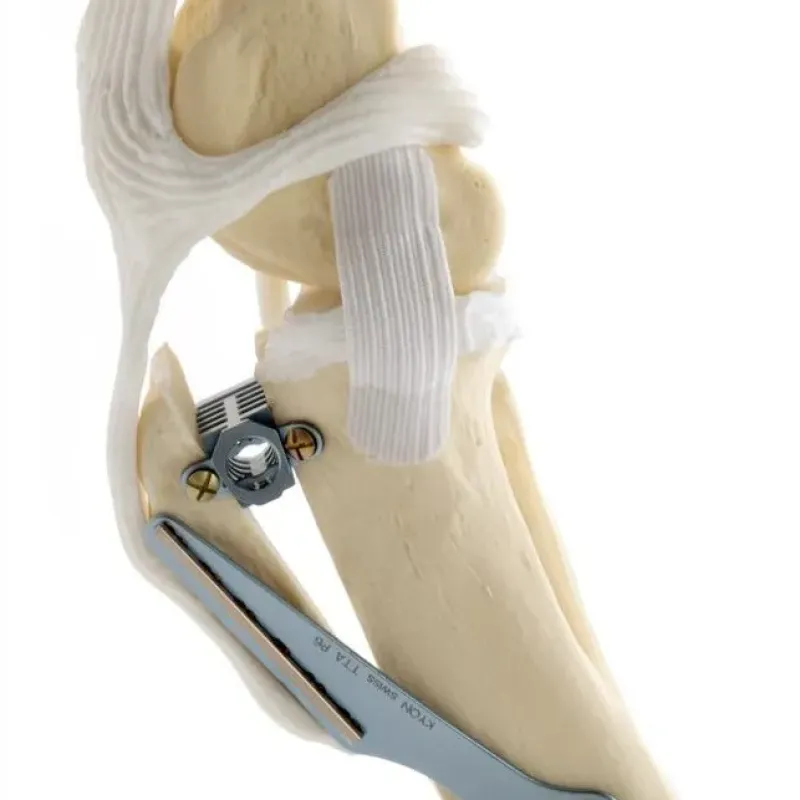

Cerrahi tedaviler, hasarlı ligamenti değiştirmeyi amaçlayan teknikler ve tibiayı keserek ve diz eklemine etki eden kuvvetleri yeniden hizalayarak bağı gereksiz hale getiren teknikler olarak kategorize edilir.

İnsanlarda bağ dokusu değiştirme için kullanılan prosedürleri taklit eden çeşitli cerrahi teknikler uzun süredir uygulanmaktadır. Köpeklerde, hastanın diz çevresindeki kendi yumuşak dokuları ile çapraz bağı taklit eden yapıları bağın yerine yerleştirme teknikleri dizin fonksiyonunu normale döndürme şansı çok düşüktür. Bunun nedeni muhtemelen değiştirilen dokuların orijinal bağ dokusu kadar sağlam olmaması ve orijinal bağ dokusunun ilk etapta başarısız olmasına neden olan aynı olumsuz biyomekanik ortamda konumlandırılmasıdır. Öte yandan sentetik lifler ve bağlar, misina benzeri naylon iplikler görece daha sağlam olsa da sıklıkla diz içerisinde inflamasyona ya da aşınmaya sebep olurlar. Her ne kadar son yıllarda gelişen nano teknoloji sayesinde doku uyumlu olduğu iddia edilen sentetik lifler yaygınlaşsa da halen en geçerli ve etkili yöntemler köpeğin bir ön çapraz bağa olan ihtiyacını ortadan kaldıran biyomekanik osteotomi teknikleridir.

Bu ameliyatlar, diz ekleminin biyomekaniğini ve geometrisini, stabiliteyi korumak için ön çapraz bağa gerek kalmayacak şekilde değiştirir. Teknikte, kemiği keserek ve yeni bir pozisyonda sabitleyerek kaval kemiğinin üst kısmının yeniden şekillendirilmesini içeren birkaç varyasyon vardır. Medicapet olarak bu tekniklerin tümünü gerçekleştiriyor olabilmekle birlikte, yapılan bilimsel çalışmalar ışığında uzun vadede en sağlıklı teknikler olarak sunulan TTA ve TPLO cerrahilerini uygulamayı tercih ediyoruz.

Bu ameliyat, TPLO ile aynı prensibi izler ve ön çapraz bağı gereksiz kılan bir geometrik ve biyomekanik bir değişikllik meytdana getirir. TTA'nın ardındaki

matematiksel prensipler, TPLO'nun ardındakilerden daha karmaşıktır; ancak temel prensip, quadriceps kas grubundan gelen çekiş yönünün değişmesinin, femur kemiğinin tibial plato eğiminden aşağı doğru kayma eğilimini nötralize eden diz eklemi boyunca bir kuvvet üretmesidir. Aslında, hem TTA hem de TPLO, tibial platoyu düz patellar tendona dik hale getirmeyi ve bunu yaparken femur kemiğinin tibia eğiminden aşağı doğru kayma eğilimini nötralize etmeyi amaçlar. Patellar ligament hasarı olan hastalarda TTA tekniği uygun olmayacaktır. Çünkü TTA tekniğini uygularken bu ligamentin çekme kuvvetinden faydalanılır.